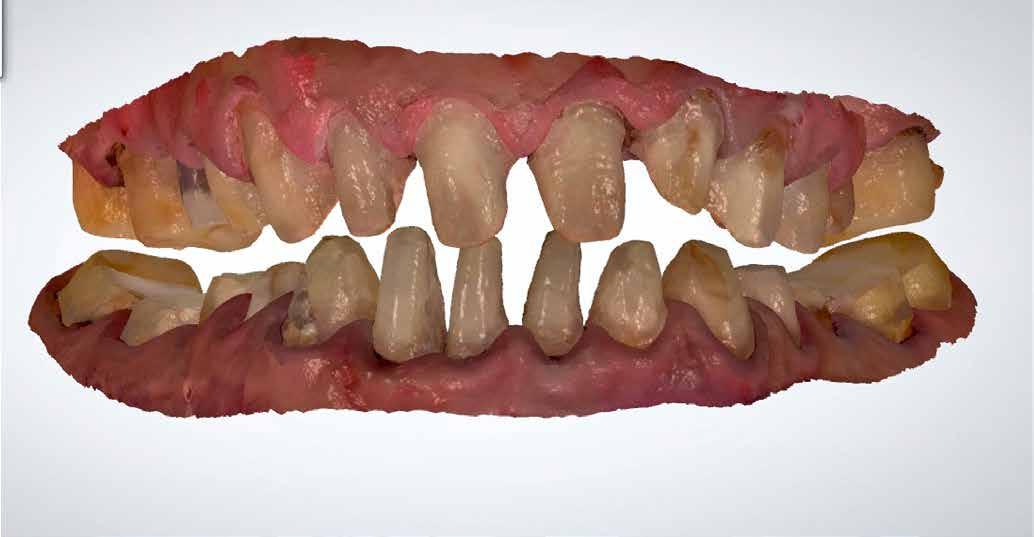

A cikkben egy fiatal nő kezelésének interdiszciplináris megközelítését foglaltuk össze, aki fogászati állapota miatt hoszszú ideje szenvedett fizikálisan és pszichésen is (1. ábra)

Amikor a 25 éves Andrea először konzultált a rendelővel, már több éve küszködött súlyos panaszokkal. Állapota két különböző betegségnek köszönhető, melyek egyrészt önmagukban, másrészt egymással kölcsönhatásban is súlyos következményekkel jártak. A fiatal nő veleszületett genetikai elváltozásban szenved, melynek tünete többek között a gyenge zománcfejlődés. Továbbá a beteget fibromyalgiával is diagnosztizálták, mely krónikus fájdalom rendellenesség, ami komoly tünetegyüttessel járó pszichés szorongás. A betegség egyik következménye az volt, hogy a páciens az elmúlt években átlagosan napi három-négyszer hányt. Az ebből fakadó savas erózió a már amúgy is veszélyben lévő fogazatot tovább roncsolta (2. ábra)

1. a–c ábrák: Kiindulási helyzet: fiatal páciens komoly fizikai és pszichés szenvedéssel.